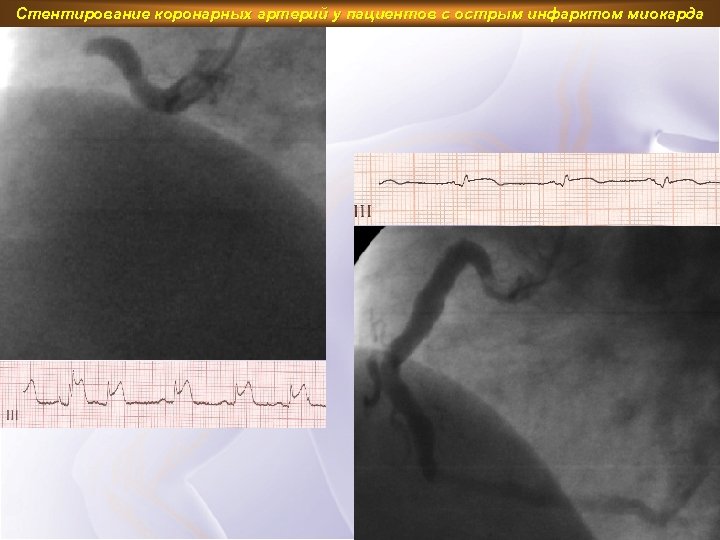

Стентирование коронарных артерий у пациентов с острым инфарктом миокарда